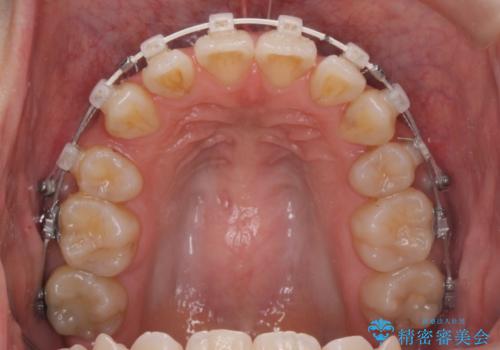

八重歯を矯正治療で治したい!

- 八重歯・がたつきのある歯並びの改善を求めて来院されました。

全部の歯が入り切るスペースがなかったため、小臼歯4本を抜去しワイヤーを用いたマルチブラケット矯正を選択しました。

歯並びの改善と共に、歯ブラシがしやすくなった!と喜んでいただくことができました。